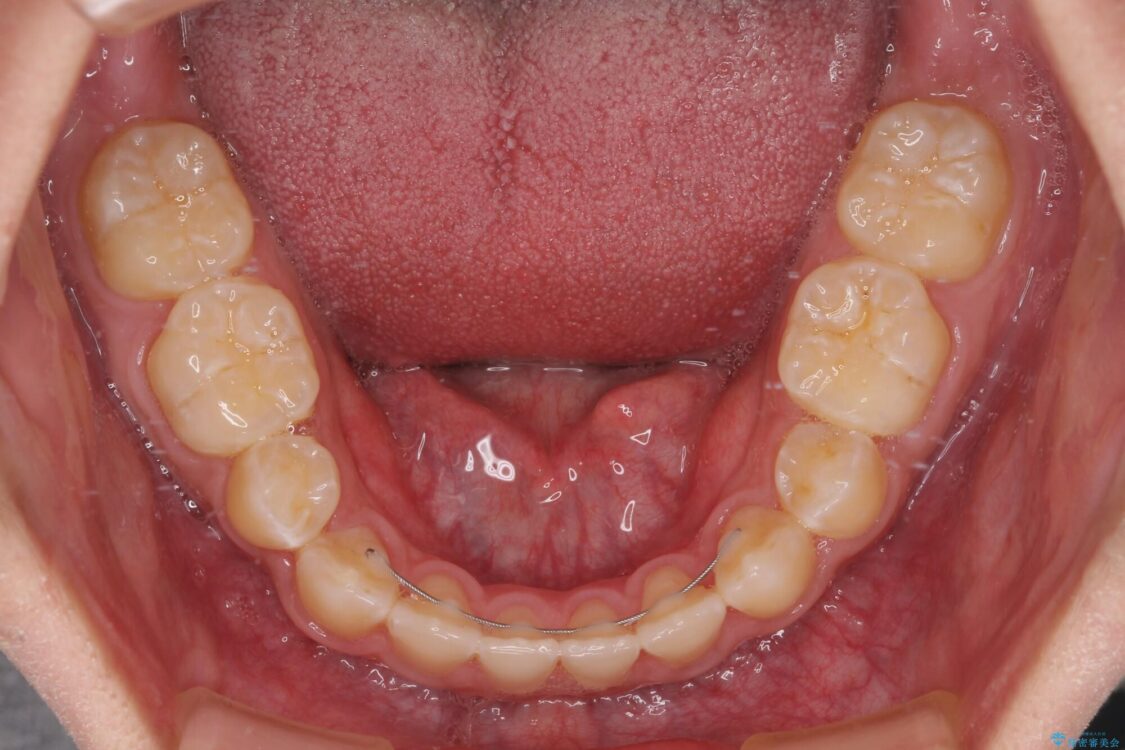

治療途中

• 口元の突出感を改善 受け口傾向の咬み合わせの抜歯矯正 治療途中画像